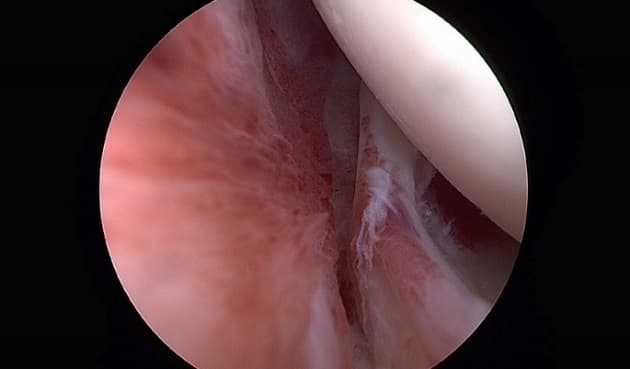

©. Artroskopibillede med akut synovitis og kontraktur af rotatorintervallet.

Frossen skulder er en idiopatisk inflammatorisk lidelse med progressiv fibrose af ledkapslen. Den opdeles den i tre stadier: det smertefulde stadie, som varer 1-3 måneder, stivheden (den frosne fase), som varer 4-12 måneder, og optøningsfasen, som varer 5-24 måneder. I statusartiklen beskriver Bak & Issakson symptomatologi og udredning og gennemgår behandlingsmulighederne. Forfatterne konkluderer, at den primære behandling er konservativ med nonsteroide antiinflammatoriske stoffer, eventuelt suppleret med kortikosteroid, som gives som intraartikulære injektioner.